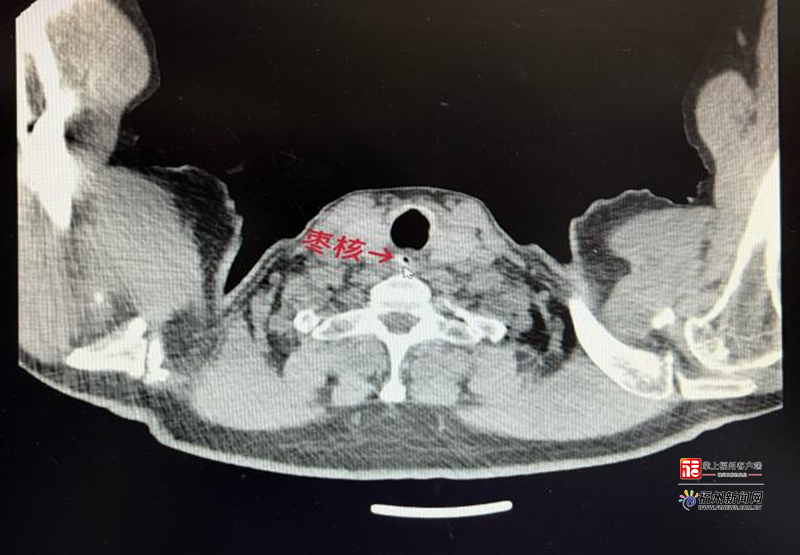

食道CT影像显示,该患者在近胸廓入口处颈胸部交界处食管偏右侧内有一大小约5mm×9mm状高低混杂密度影。(福建省老年医院 供图)

明天是元宵佳节,在阖家团聚共享汤圆、美食之际,餐桌上的安全隐患不容忽视。近日,福建省老年医院急诊科接诊了一位72岁的郑老先生,他在早餐食用寓意吉祥的红枣粥时,不慎被枣核卡住咽喉,经紧急内镜手术才取出两端尖锐的枣核。